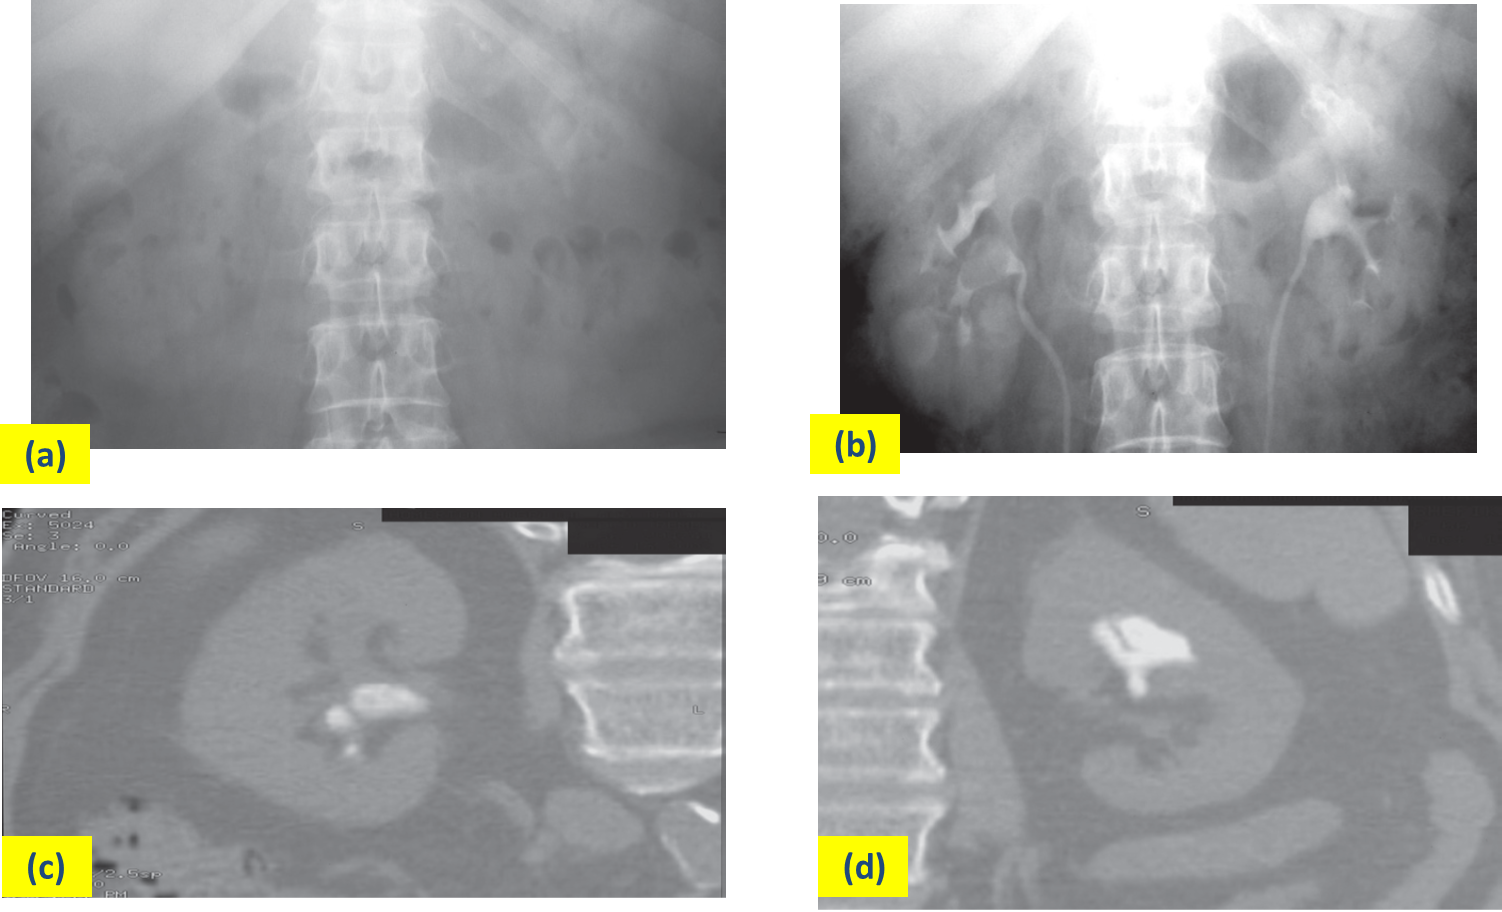

All renal calculi have high attenuation on CT

(a) IVU control film. Renal stones are not visible on the right and are very poorly visualized on the left. (b) IVU following intravenous contrast. Filling defects are seen in the right lower calix and pelvis and in the left upper pole calices . (c, d) CT of the kidneys in the same patient with no contrast medium, reformatted in the coronal plane, demonstrating the renal stones in both the right (c) and left (d) kidneys.